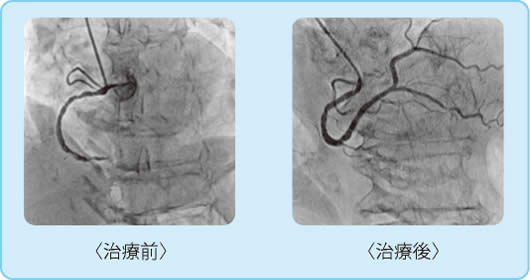

【ABL/カテ検査】 検査・治療|循環器内科|大阪市立総合医療センター循環器センターの詳細情報

検査・治療|循環器内科|大阪市立総合医療センター循環器センター。神戸アドベンチスト病院 | カテーテル検査・治療。Argyle™ Fukuroi CV カテーテル セルジンガー キット。あんず⚠︎2冊とも裁断済みです⚠︎これから始める カテーテルアブレーションこれから始める 心臓カテーテル検査発送は7/11となります。ACHDのカテーテル治療:現在まで,そして未来へ。よろしくお願い致します。病気がみえる vol.3 糖尿病・代謝・内分泌。